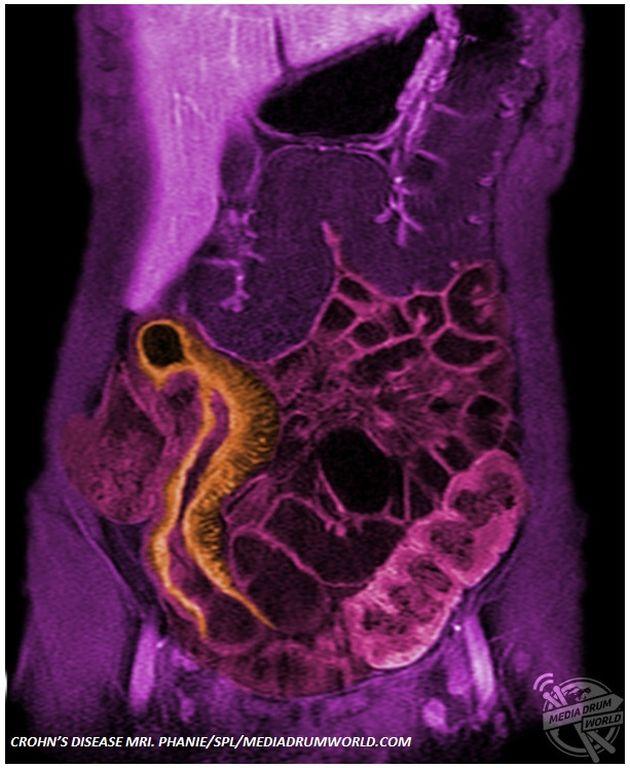

Μερικές από τις σοβαρότερες και πιο επίπονες ασθένειες που δυστυχώς αντιμετωπίζουν πολλοί άνθρωποι, αποτυπώνονται μέσα από φωτογραφίες έγχρωμες. Ασθένειες όπως ο καρκίνος και η αρθρίτιδα γίνονται φωτογραφίες και παίρνουν μορφή.

Από μια ακτινογραφία των δαχτύλων ασθενούς με αρθρίτιδα μέχρι έναν υπέρηχο ενός διογκωμένου προστάτη, οι φωτογραφίες παρουσιάζουν ασθένειες που πλήττουν χιλιάδες ανθρώπους ανά τον κόσμο, προκαλώντας έντονο πόνο και σημαντικούς περιορισμούς στην καθημερινότητα.